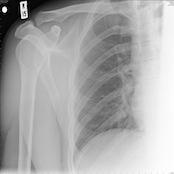

Broken Bones and Fractures

No matter where in the body the pain exists, X-ray techs can position the person to get just the angle they need to take a look inside. Broken bones are easily diagnosed with X-rays, as well as most fractures.